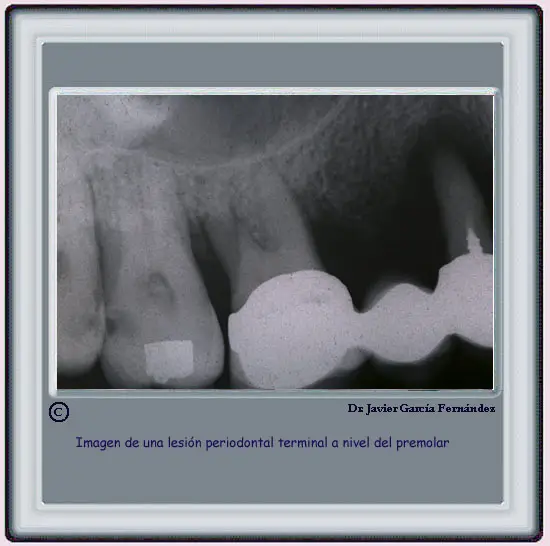

image211